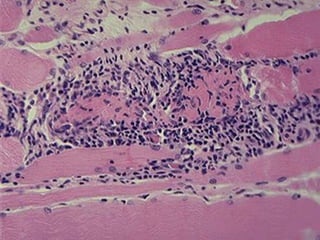

A, Dermatomyositis. Note the rash affecting the eyelids.

B, Dermatomyositis. The histologic appearance of muscle shows

perifascicular atrophy of muscle fibers and inflammation..

Downloaded from: Robbins & Cotran Pathologic Basis of Disease (on 28 September 2009 11:10 PM)

© 2007 Elsevier